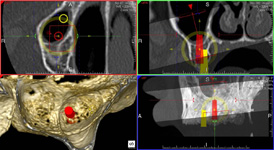

Jedná se o plánovací program, který využívá dat získaných při vyšetření pomocí přístroje New Tom. Tento program umožňuje tříprostorovou počítačovou simulaci při plánování pozic implantátů.

Součástí programu je i databáze, ve které mohou být uloženy všechny typy implantátů od všech výrobců, včetně jejich délek, průměrů i tvarů.

Lékař si vytvoří všechny typy zobrazení potřebných pro naplánování – tedy 2D snímky (panoramatický), příčné řezy i 3D model.

Vidí zde i důležité anatomické útvary – čelistní dutinu, průběh nervu atd. Po proměření množství kosti – šířky i výšky vybere z databáze vhodný typ implantátu a umístí ho do požadované lokality.

Ihned vidí jeho pozici ve všech 3 rovinách a na všech snímcích i 3D modelu. Může upravovat podle potřeby jeho pozici, sklon atd.

Všechny vybrané a správně umístěné simulované implantáty se ukládají do „počítačové karty“ pacienta s jejich pozicí, délkou, průměrem, typem i sklonem.

Jedná se o externí plánovací program, spojený se zubní laboratoří a frézovacím centrem, který využívá dat získaných z 3D rentgenu čelisti, otisku zubů a dásně (scanu zubů a dásně) a finálního návrhu protetické náhrady.

Tento program umožňuje tříprostorovou počítačovou simulaci při plánování pozic implantátů. Součástí programu je i databáze, ve které mohou být uloženy všechny typy implantátů od všech výrobců, včetně jejich délek, průměrů i tvarů.

Vidí zde i důležité anatomické útvary – čelistní dutinu, průběh nervu atd. Po proměření množství kosti – šířky i výšky vybere z databáze vhodný typ implantátu a umístí ho do požadované lokality. Ihned vidí jeho pozici ve všech 3 rovinách a na

všech snímcích i 3D modelu. Může upravovat podle potřeby jeho pozici, sklon atd.

Všechny vybrané a správně umístěné simulované implantáty se ukládají do „počítačové karty“ pacienta s jejich pozicí, délkou, průměrem, typem i sklonem. V programu také lékař navrhuje chirurgické šablony pro řízenou nebo navigovanou implantaci.